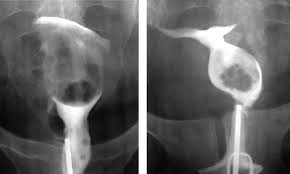

Гистеросальпингография

Дополнительным методом диагностики мочеполового туберкулеза у женщин является гистеросальпингография – рентгенологический метод исследования. С помощью него можно проверить:

- Смещение матки при образовании спаек;

- Внутриматочные синехии – спайки;

- Изменение контура маточных труб, их непроходимость;

- Кальцификаты в ткани яичников и местных лимфоузлов.